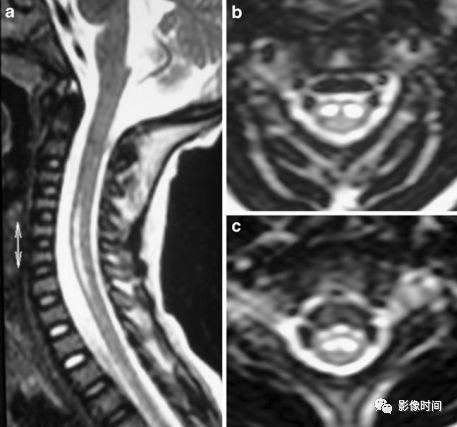

无骨折脱位型脊髓损伤 (Spinal cord injury without radiographic abnormality,SCIWORA) 是指在 X 线或 CT 检查未发现骨折或脱位的脊髓损伤,主要见于儿童,SCWORA 的创伤机制包括过度伸展、屈曲、牵引和脊髓缺血损伤。

MRI:

脊髓长节段或短节段病灶,颈胸髓常见

T2WI 高信号;T1WI 低信号